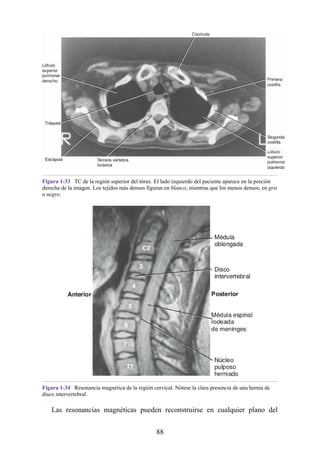

Sinergista: en muchas localizaciones del cuerpo, el músculo agonista

atraviesa varias articulaciones antes de llegar a la articulación donde tiene lugar

la acción principal. Para prevenir movimientos no deseados en una articulación

intermedia, los músculos sinergistas se contraen y estabilizan las articulaciones